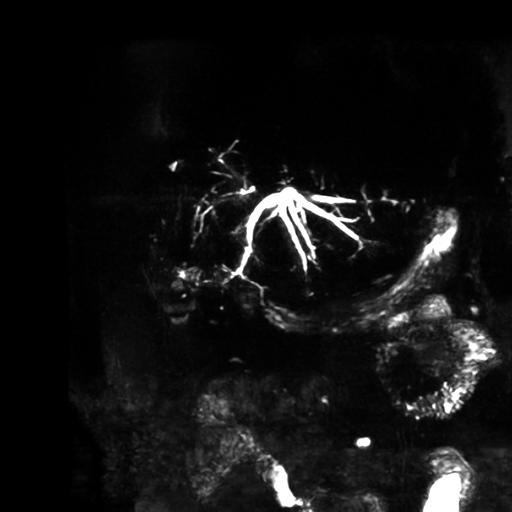

En los últimos años, revisiones y reportes de casos han mostrado con claridad cómo la imagen –especialmente la colangiorresonancia magnética (MRCP)– se ha convertido en la herramienta central para entender esta nueva “normalidad” biliar postquirúrgica y distinguirla de la patología. La MRCP permite mapear con precisión la dilatación de los conductos intrahepáticos, valorar la permeabilidad de la anastomosis, identificar segmentos hepáticos atróficos y orientar el abordaje terapéutico, ya sea endoscópico, percutáneo o quirúrgico.

Recent reviews and case reports have highlighted how imaging—particularly magnetic resonance cholangiopancreatography (MRCP)—has become central to understanding this new postoperative biliary “normal” and distinguishing it from disease. MRCP enables precise mapping of intrahepatic duct dilatation, assessment of anastomotic patency, identification of atrophic liver segments and guidance of therapeutic strategies, whether endoscopic, percutaneous or surgical.

HALLAZGOS IMAGENOLOGICOS

Se observa dilatación de las vías intra hepáticas a expensas de sus ramas hepáticas derecha, anterior y posterior, hepática izquierda y hepática común. El hepático común da la apariencia de estar anastomosado a un asa de intestino, lo que sugiere la posibilidad de una cirugía entero biliar.

No se logra observar el colédoco.

5. Relación imagen–fisiopatología

En la práctica radiológica, esta fisiopatología se traduce en hallazgos como:

o Dilatación segmentaria o difusa de los conductos intrahepáticos proximal a la anastomosis.

o Estrechamiento focal o filiforme en el sitio de la unión bilioentérica.